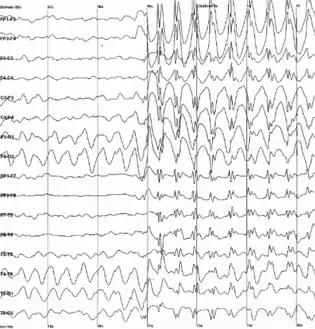

| Generalized 3 Hz spike and wave discharges in a child with childhood absence epilepsy. | |

EEG findings

Findings that strongly suggest LGS include consistent slow spike-wave (< 3 hertz [Hz]) on awake EEG. The complexes typically consist of a spike (duration < 70 milliseconds) or a sharp wave (70-200 milliseconds), followed first by a positive deep trough, then a negative wave (350-400 milliseconds). Not every wave is preceded by a spike. Bursts increase and decrease without clear onset and offset. Slow spike waves may occur during seizure or between seizures, or may occur in absence of any observable clinical changes which helps distinguish pattern from extended 3-Hz spike-wave discharges.